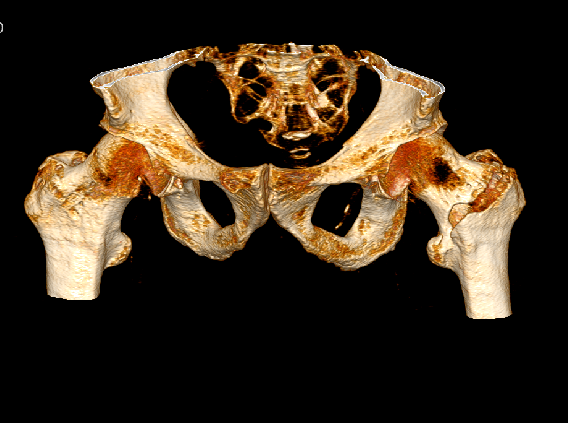

影像资料:

骨盆正位

髋部CT

髋部CT+骨三维

左股骨粗隆骨折,伴心动过缓,三度房室传导阻滞。阿托品试验阴性。